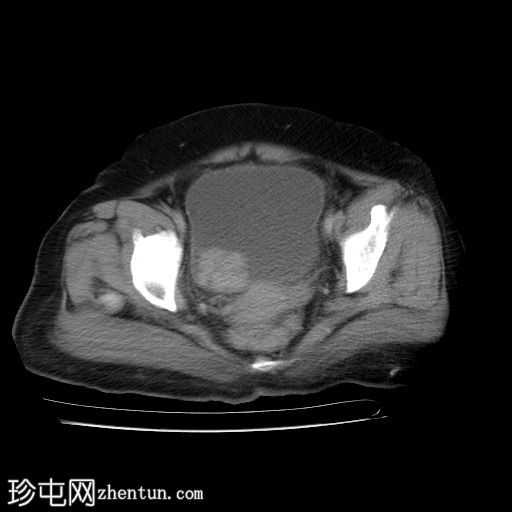

轴位增强扫描

延迟期

3.jpg

膀胱内可见一边界清晰、不规则、可移动的软组织病变(CT值65 HU),直径约40 mm。病变无钙化,增强扫描后无强化。首要鉴别诊断为血肿。

采用俯卧位CT扫描显示病变活动度。